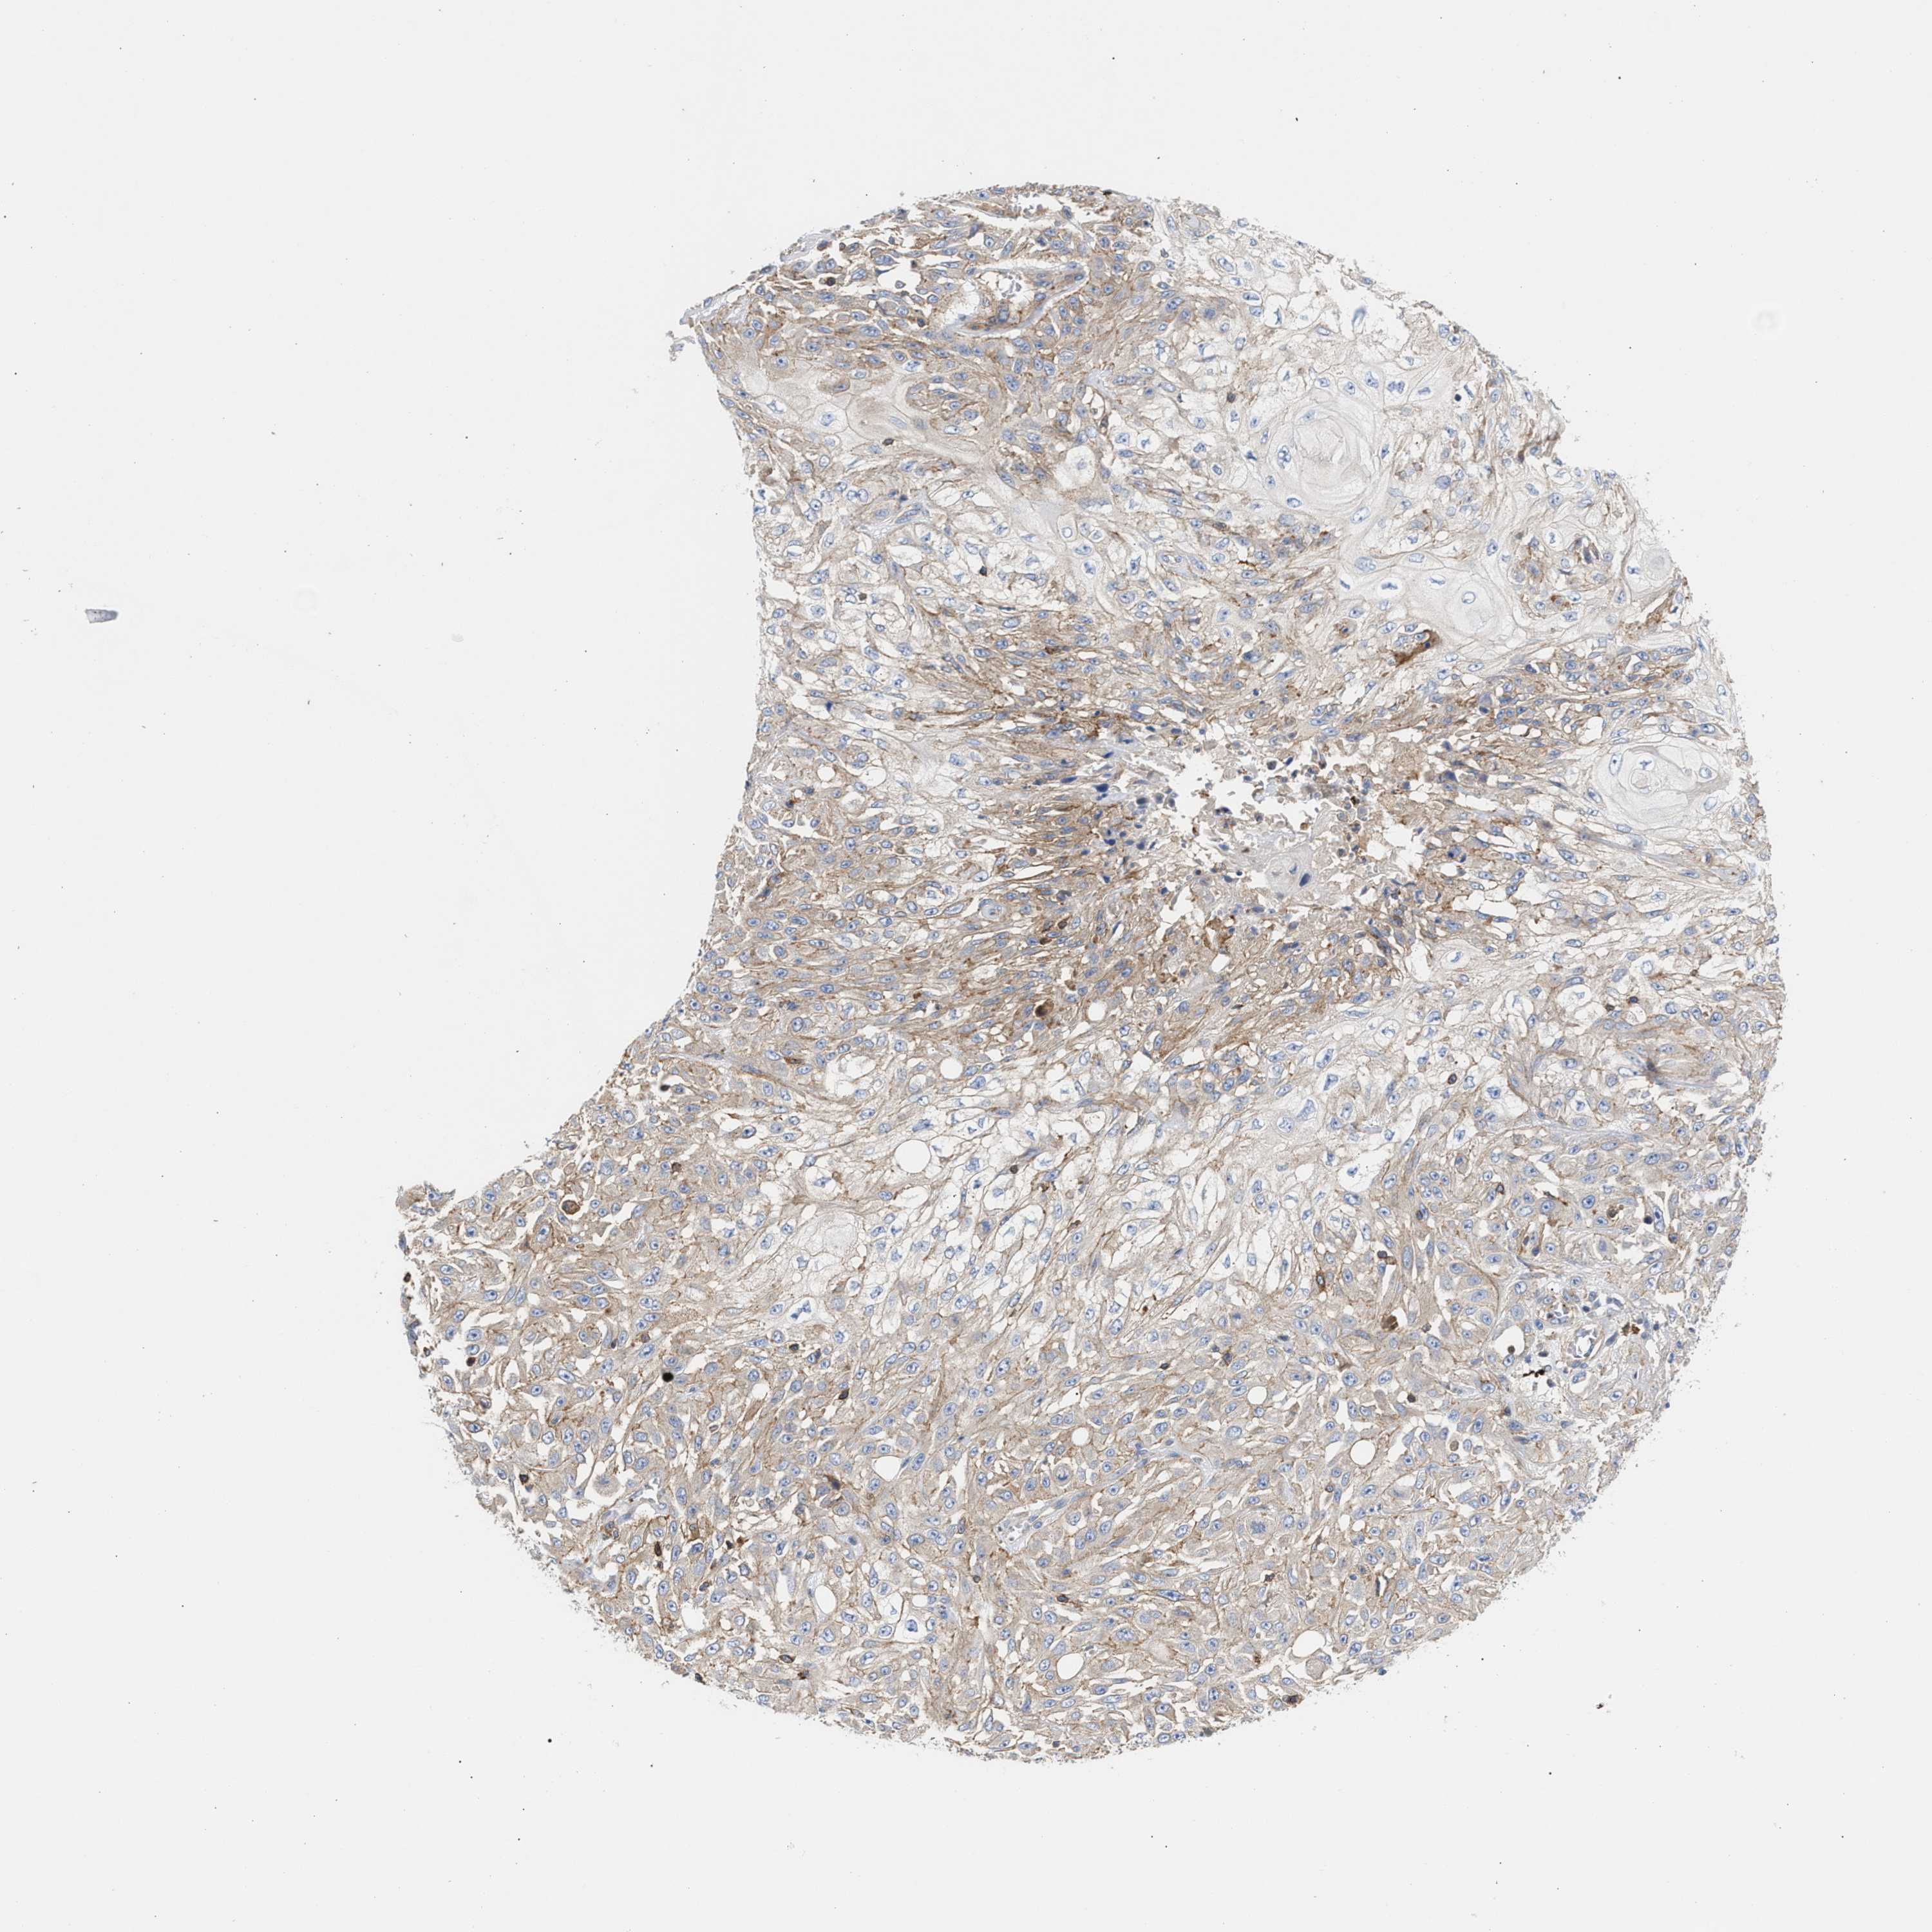

SKIN CANCER - Protein expressioni

A mouse-over function shows sample information and annotation data. Click on an image to view it in a full screen mode. Samples can be filtered based on level of antibody staining by selecting one or several of the following categories: high, medium, low and not detected. The assay and annotation is described here.

Antibody stainingi

Antibody staining in the annotated cell types in the current human tissue is reported as not detected, low, medium, or high, based on conventional immunohistochemistry profiling in selected tissues. This score is based on the combination of the staining intensity and fraction of stained cells.

Each image is clickable and will lead to virtual microscopy that enables deeper exploration of all samples and also displays staining intensity scores, fraction scores and subcellular localization as well as patient and tissue information for each sample.

Antibody HPA021823

Antibody HPA064677

Basal cell carcinoma

Squamous cell carcinoma, NOS

Squamous cell carcinoma, metastatic, NOS

BCC, high aggressive